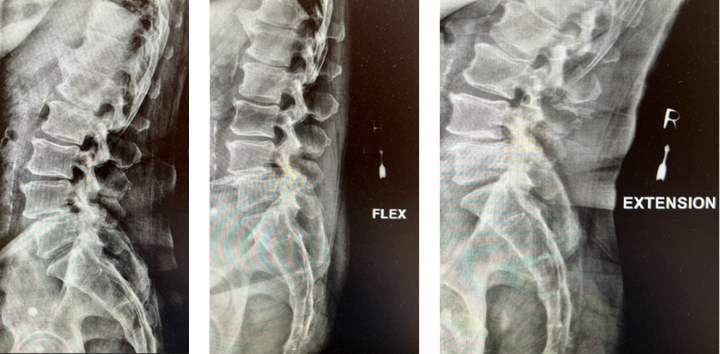

Revision Surgery Treats Intractable Neck Pain & Cervical Deformity

Author: Benjamin R. Cohen M.D., F.A.A.N.S., F.A.C.S., Read More!